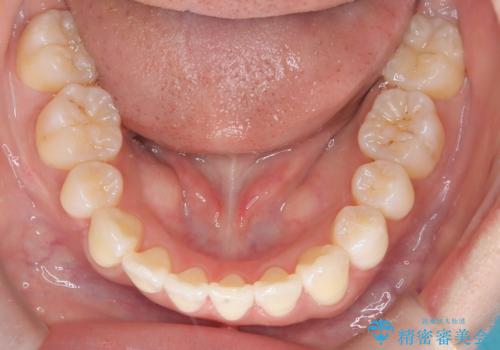

- 出っ歯、ガタツキ、噛み合わせが気になるとのことで来院された患者様です。

小臼歯を抜歯することでスペースを作り、前歯を下げて口元を下げ、Eラインを改善する治療方針としました。

表側のワイヤーは見た目が気になるとのことで、上の歯だけ裏側に付くハーフリンガルという装置で治療を行いました。